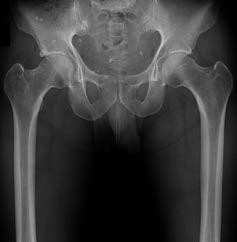

Question 25:

A 13-year-old obese male underwent in situ single-screw pinning for a severe, unstable slipped capital femoral epiphysis (SCFE) 6 months ago. He now complains of progressive hip stiffness and pain. Radiographs demonstrate marked concentric joint space narrowing of the affected hip without evidence of avascular necrosis. What is the most likely diagnosis?

Correct Answer: Chondrolysis

Explanation:

Chondrolysis is a known complication of SCFE, characterized by acute articular cartilage destruction, concentric joint space narrowing (typically <3 mm), stiffness, and pain. It is more common in severe slips, unstable slips, and historically with spica cast immobilization or unrecognized intra-articular hardware penetration, though it can occur idiopathically post-slip.